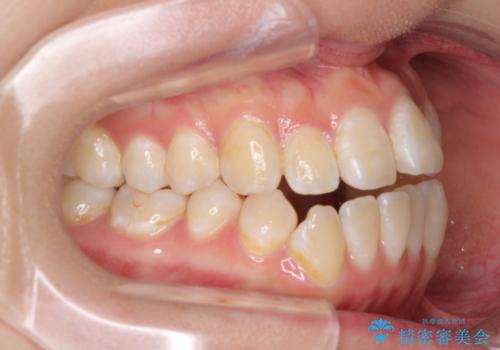

- 上下前歯の隙間と、外側を向いていて歯磨きのしにくい奥歯を気にして来院された患者様です。

下顎前歯が1本欠損しており、上下アーチはアンバランスとなりますが、インビザラインを用いて上下の隙間を改善しながら歯列を整えることとしました。

外側を向いている奥歯は、内側にアンカースクリューを埋入して牽引の固定ゲント氏、部分的にワイヤー装置を用いることで歯列に納めることとしました。